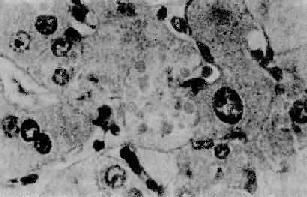

2.酒精性肝炎(alcoholic hepatitis)在有临床肝症状表现的病例,常出现3种病变:肝细胞脂肪变性,酒精透明小体(alcoholic hyalin,AH 图10-42)形成和灶状肝细胞坏死伴中性粒细胞浸润。

图10-42 酒精性肝炎

图中央区肝细胞浆内见成群的酒精透明小体